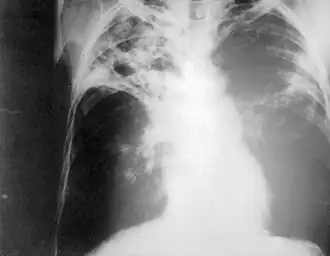

![]() Chest radiography showing advanced bilateral pulmonary tuberculosis. Source: CDC | |

Chest photofluorography, or abreugraphy (better known as mass miniature radiography in the UK and miniature chest radiograph in the US), is a photofluorography technique for mass screening for tuberculosis using a miniature (50 to 100 mm) photograph of the screen of an X-ray fluoroscopy of the thorax, first developed in 1936.